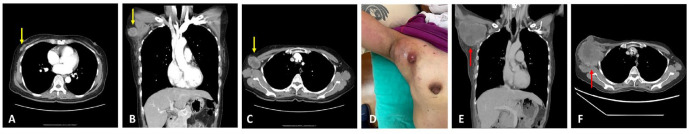

化生性乳腺癌是一种浸润性癌,肿瘤上皮向间质样上皮分化率高。它只占所有乳腺癌的不到1%。虽然80%至90%的化生性乳腺癌是三阴性癌症,但它们的预后通常比其他三阴性乳腺癌(tnbc)更差。化生癌对细胞毒性化疗也常常是难治的。在此,我们报告了一例61岁的女性患者,在右腋窝尾乳腺组织中表现为一个孤立的带梗肿块,活检显示化生性乳腺癌伴软骨样分化。新辅助化疗和免疫治疗均失败。尽管她接受了减体积手术,但手术前肿瘤的再生速度更快。尽管接受了姑息性化疗,患者还是在手术后11周死亡。这个病例引起医生的注意,早期识别和手术可能比化疗更有利于对抗化生乳腺癌。

Metaplastic breast carcinoma is an invasive carcinoma with a high differentiation rate of the neoplastic epithelium toward mesenchymal-like epithelium. It comprises of only less than 1% of all breast cancers. Although 80% to 90% of metaplastic breast carcinomas are triple-negative cancers, they usually have worse outcomes than other triple-negative breast cancers (TNBCs). Metaplastic carcinoma is also often refractory to cytotoxic chemotherapy. Here, we reported a case of a 61-year-old female patient, presenting with a solitary and pedunculated mass in the right axillary tail breast tissue, whose biopsy revealed metaplastic breast carcinoma with chondroid differentiation. She had failed neoadjuvant chemotherapy and immunotherapy. Although she received debulking surgery, the tumor regrew even faster before surgery. Despite receiving palliative chemotherapy, the patient died 11 weeks after surgery. This case draws attention to physicians that early recognition and surgery may be more beneficial than chemotherapy in combating metaplastic breast carcinoma.